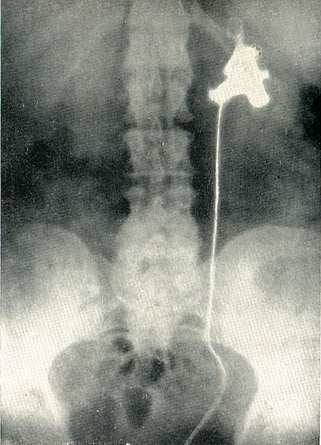

Діагноз простий, коли при цистоскопії, виконаної з приводу гематурії, виявляється, що стирчить з гирла сечоводу ворсіна пухлини. Характерно поява крові з сечоводу при травмуванні пухлини кінчиком сечовідного катетера. Найбільш важливим методом діагностики є ретроградна пієлографія, при якій виявляється дефект наповнення ниркової миски, іноді з розширенням і деформацією її (рис. 106).

Рис 106. Пухлину миски лівої нирки. Дефект наповнення на ретроградної пиелограмме